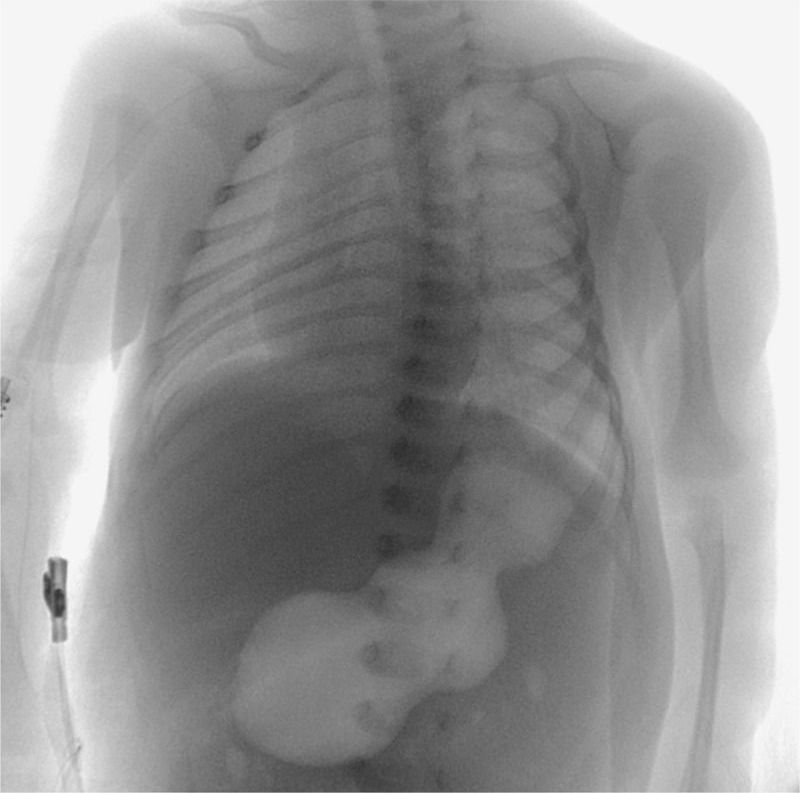

A 23-day-old male infant was brought to the emergency department because of nonbilious vomiting that had increased in frequency over a period of 5 days. Findings from the clinical examination were notable for mild dehydration and a possible olive-sized mass, approximately 2 cm in diameter, that was detected on palpation of the abdomen. An upper gastrointestinal radiographic series was obtained (ultrasonography was not readily available as the initial test), and the findings showed a distended, air-filled stomach with undulating contours, known as the “caterpillar” sign. This sign is visible when active hyperperistaltic waves come to an abrupt stop at the pylorus — a finding that is suggestive of hypertrophy. Abdominal ultrasonography was then performed, and the results showed a pyloric wall width of 4.5 mm, a pyloric diameter of 25.0 mm, and a pyloric channel length of 24.0 mm. Given that a pyloric wall width of 3 mm is considered to be the cutoff for the normal range, the 4.5-mm value in this infant confirmed the diagnosis of infantile hypertrophic pyloric stenosis. The infant underwent an open pyloromyotomy and had no complications from the procedure. He was discharged home 2 days later and was able to receive full feedings. At follow-up 3 months later, he remained well.